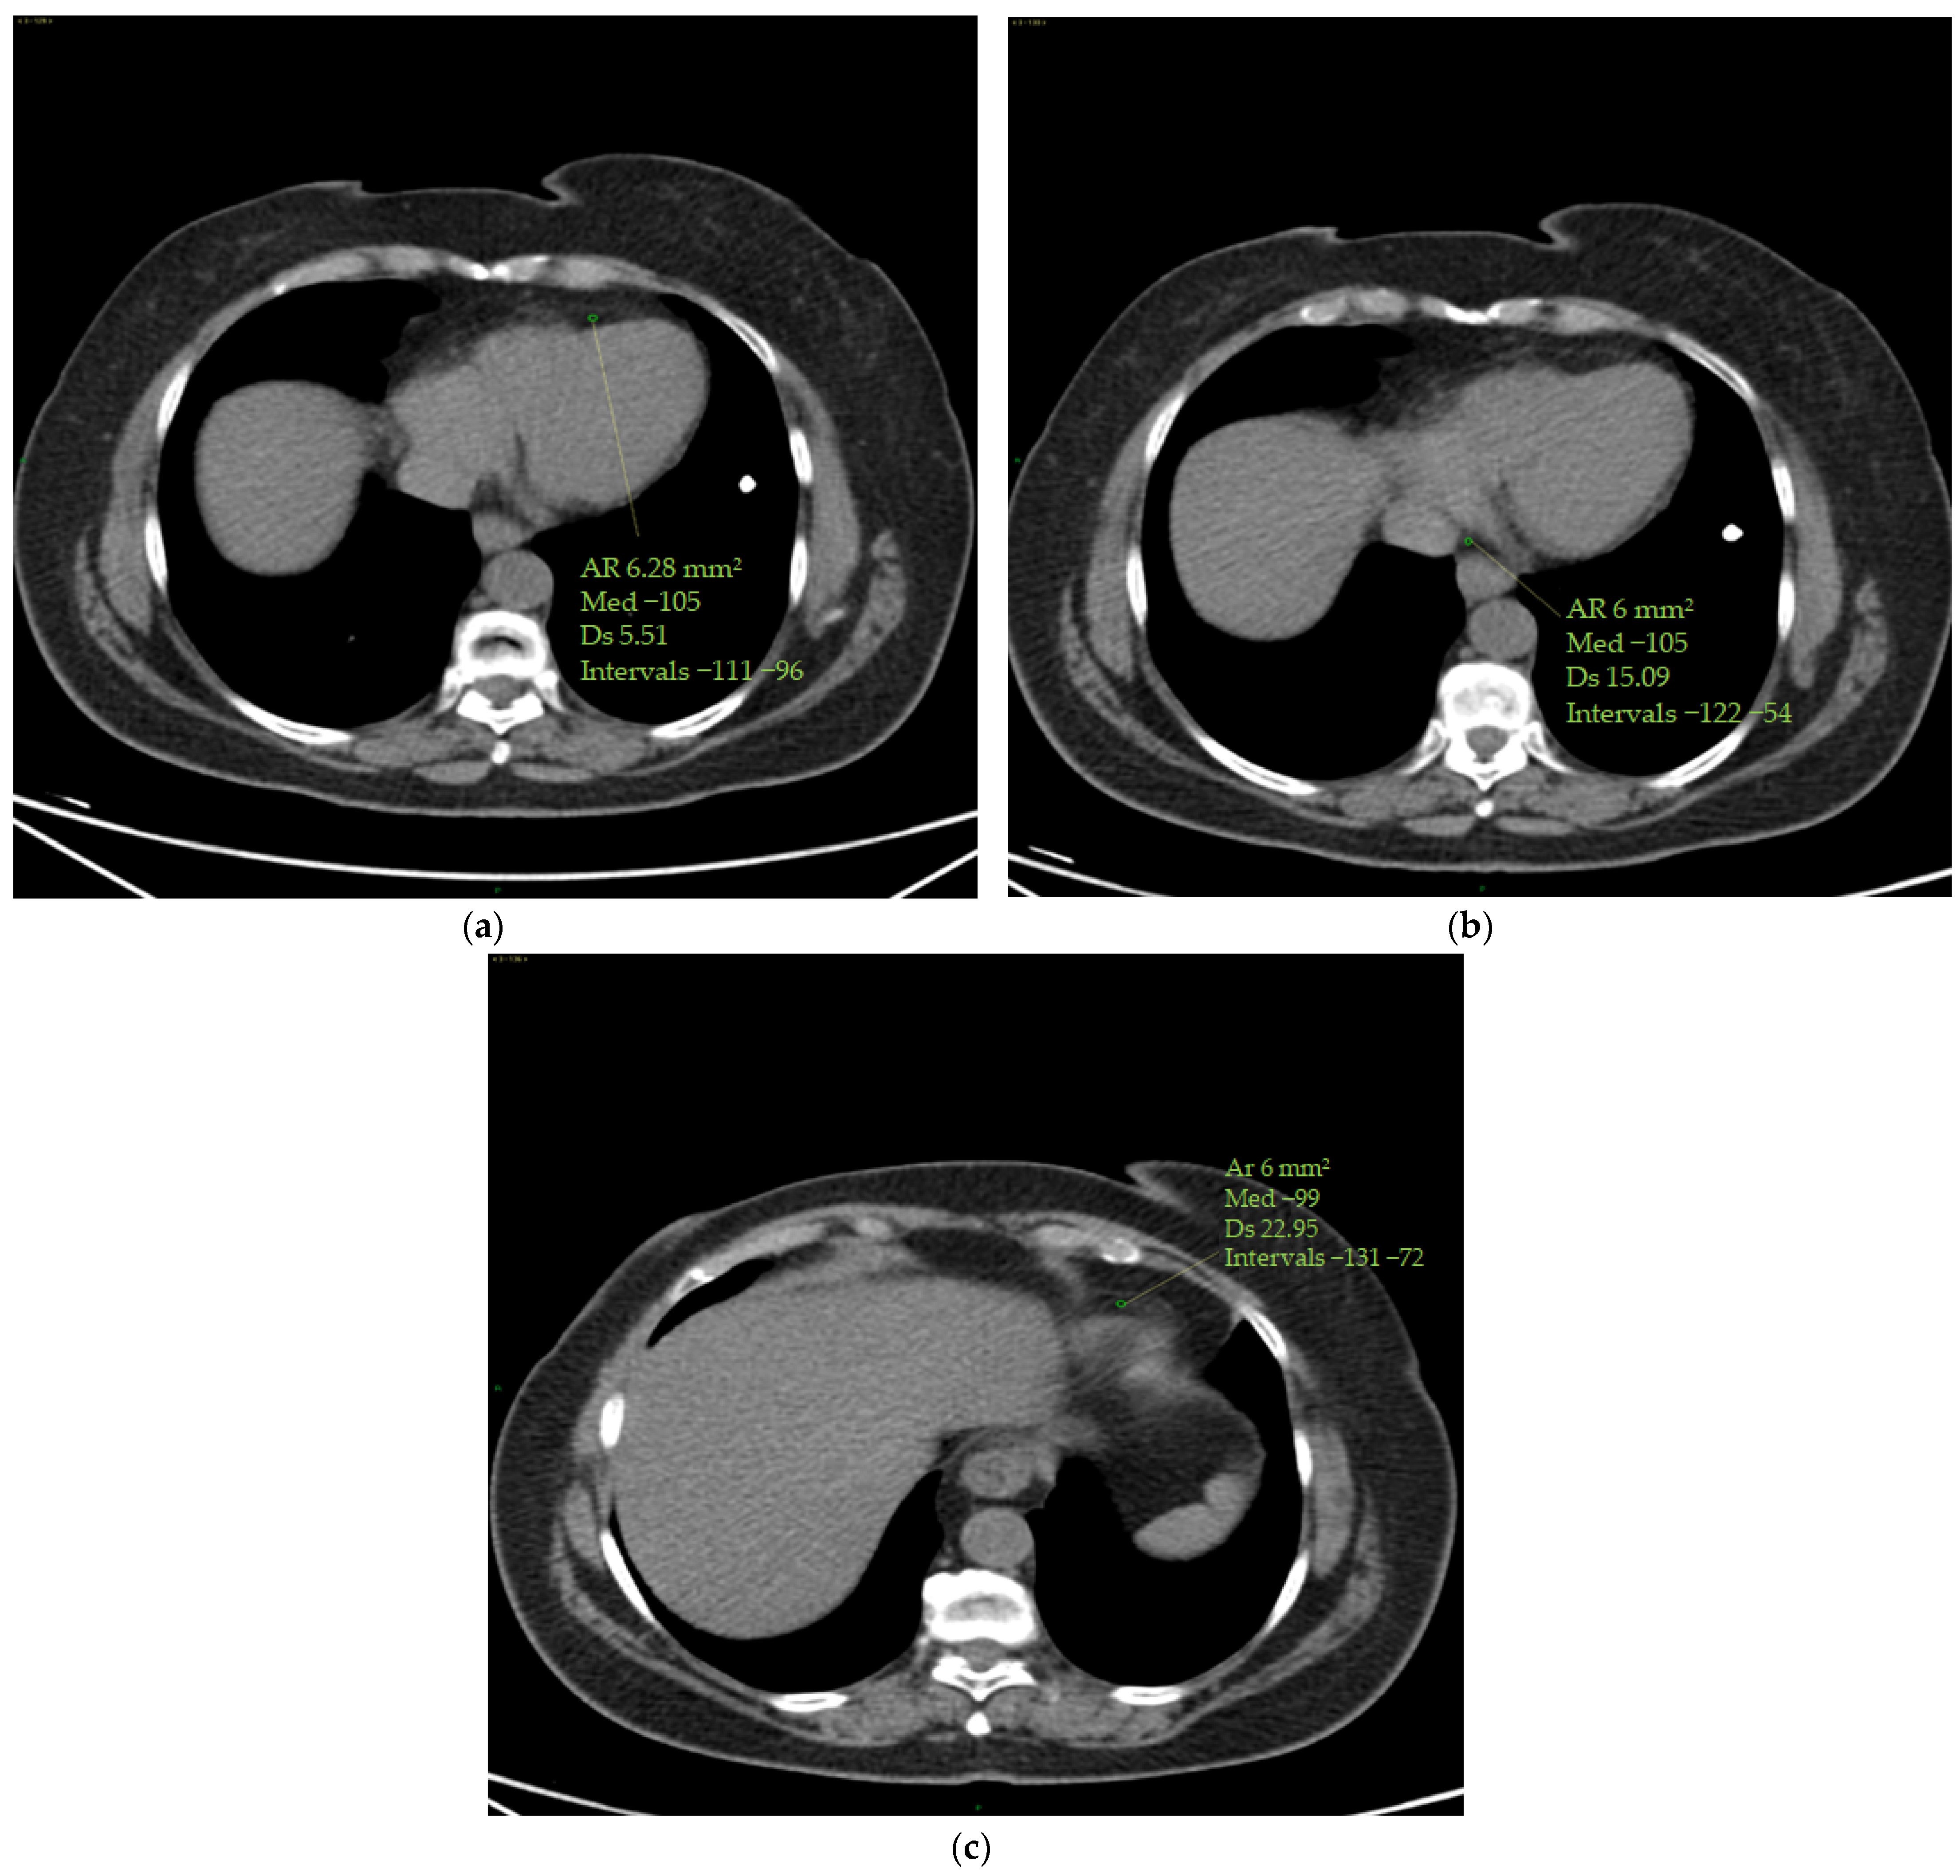

To calculate the ECV, the operator selected the optimum slice to observe the four cardiac chambers from an axial perspective.

The measurements were taken by manually inserting one ROI in the left ventricle’s ‘blood’ pool and a second ROI in the middle of the interventricular septum, avoiding papillary muscles. The same ROIs were set in the pre-contrast and post-contrast scans (portal phase). ROIs were measured in two stages (basal and portal) at time 0 and at the end of chemo-immunotherapy to provide Hounsfield units (HUs) to be used in the ECV calculation.

Standard deviations of ROIs were calculated to avoid contamination of myocardial HU measurements by motion artefacts. Altered values were not considered in this study (Figure 1).

Figure 1. ECV measurement. Myocardial and blood pool HU values were obtained on the four cardiac chambers’ projection from an axial perspective on CT scans by manually inserting one ROI (with a mean area of 6 mm2 ca) in the middle of the interventricular septum and a second ROI (with a mean area of 6 mm2 ca) in the left ventricle’s ‘blood’ pool. Papillary muscles were avoided. The ROIs were set to the same level both in the pre-contrast scans (a) and in the post-contrast scans (at portal phase) (b). ROI standard deviations were calculated to avoid contamination of myocardial HU measurements by motion artefacts. The figure shows an example of the area of the region of interest (Ar ROI), the mean (med), the standard deviation (Ds) and the range(intervals) of hounsfield units measured.